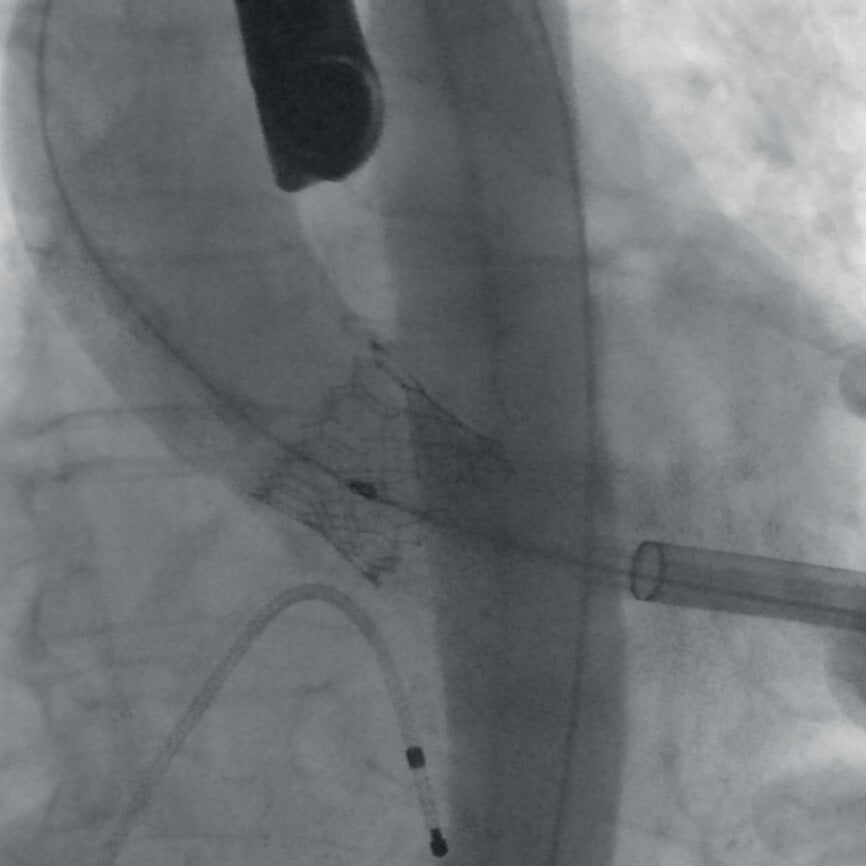

Полное отсутствие искажений снимков в сочетании с высоким динамическим диапазоном широко востребованы как при сложных операциях в нейрохирургии, сосудистой хирургии, инвазивной радиологии, так и в гибридных областях применения, а также в ортопедии, травматологии. В сосудистой хирургии особенно важны высокий динамический диапазон и пространственное разрешение, обеспечивающие детальную визуализацию даже мельчайших сосудов. Специализированное программное обеспечение SmartVascular позволяет проводить настройку системы для васкулярных операций и сосудистой хирургии.

Впервые в мировой практике в Vision RFD 3D используется невероятно компактный моноблочный генератор для импульсной рентгеноскопии с увеличенной резервной мощностью и вращающимся анодом рентгеновской трубки для улучшения качества изображений при минимальной интенсивности облучения. Продолжительность импульсов можно регулировать в диапазоне от 7 до 40 мс, что существенно повышает четкость снимков. Vision RFD 3D отлично подходит для использования в клинических процедурах типа: чрескожная транслюминальная коронарная ангиопластика или коронарная ангиография.